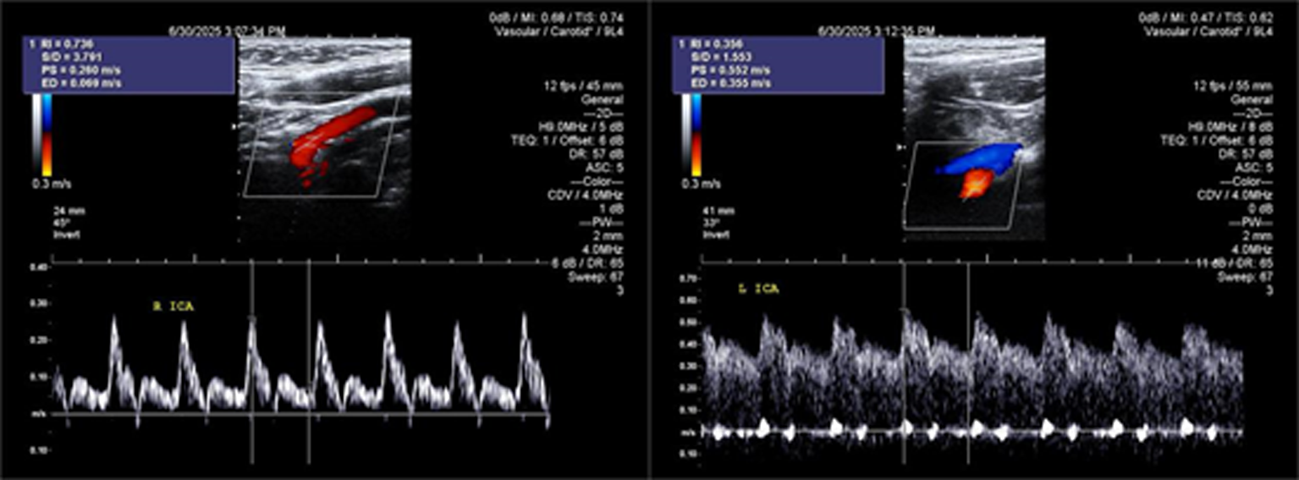

Objective To summarize diagnostic and differentialdiagnostic approaches for initial detection of moyamoya disease (MMD) using carotid ultrasound (CAU). Methods We report two patients who were first diagnosed with MMD by CAU and summarize the diagnostic reasoning and differential considerations. Relevant literature was reviewed to contextualize these findings. Results Case 1: A 57-year-old female presented with a >10 year history of dizziness and headache with recurrence over 3 days. CAU showed a reduced diameter of the left internal carotid artery (ICA), decreased flow velocity, and a lower resistance index, raising suspicion for severe intracranial stenosis or occlusion and prompting clinical exclusion of MMD. Magnetic resonance angiography (MRA) confirmed severe stenosis of the left ICA with absent distal branches and multiple small abnormal vascular networks in the left suprasellar region, consistent with MMD. Case 2: A 23-year-old male presented with dizziness for >1 year and transient right upperlimb weakness for 1 day. CAU and transcranial color Doppler (TCCD) showed a narrowed right ICA with reduced flow velocity and increased resistance index, suggesting chronic occlusion of the right middle cerebral artery and stenosis of the left middle cerebral artery, raising the possibility of MMD. MRA demonstrated an indistinct right ICA and right middle cerebral artery and narrowing of the left middle cerebral artery. On followup, the patient was diagnosed with MMD. Conclusion When CAU reveals a small internal carotid artery diameter accompanied by slowed flow velocity, clinicians should perform a comprehensive evaluation-including TCCD and further vascular imaging-to avoid missed or incorrect diagnoses of MMD.